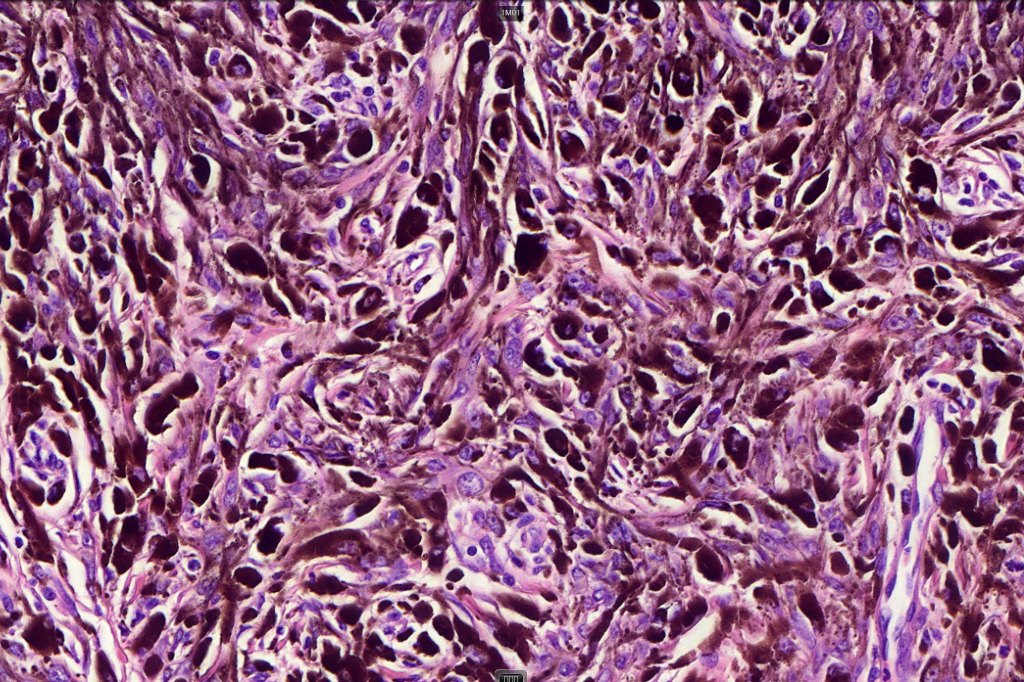

•Composed of an admixture of large epithelioid melanocytes with vesicular nuclei containing a very prominent nucleolus (fried egg cells), spindle cells, dendritic cells & melanophages

•The epithelioid cells are typically very uniform

•Few mitoses

•Absent necrosis & lymphovascular invasion